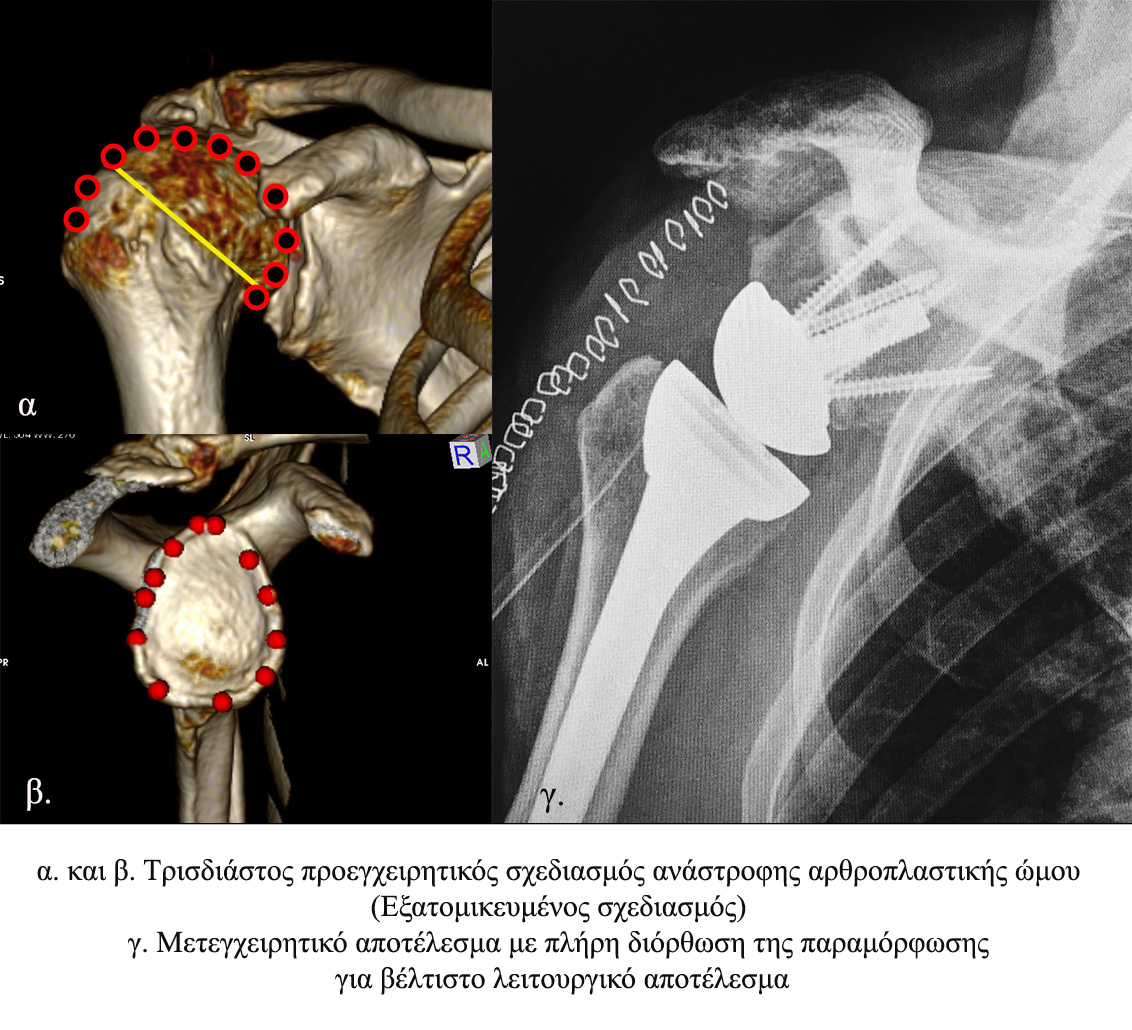

Η ομάδα μας έχει αναπτύξει νέα μέθοδο για την προεγχειρητική και μετεγχειρητική αξιολόγηση της βέλτιστης θέσης μιας αρθροπλαστικής ώμου, ώστε να μπορεί να προβλεφθεί το καλύτερο λειτουργικό αποτέλεσμα. H μέθοδος έχει γίνει δεκτή σε επιστημονικό περιοδικό για δημοσίευση. (Boutsiadis et al).